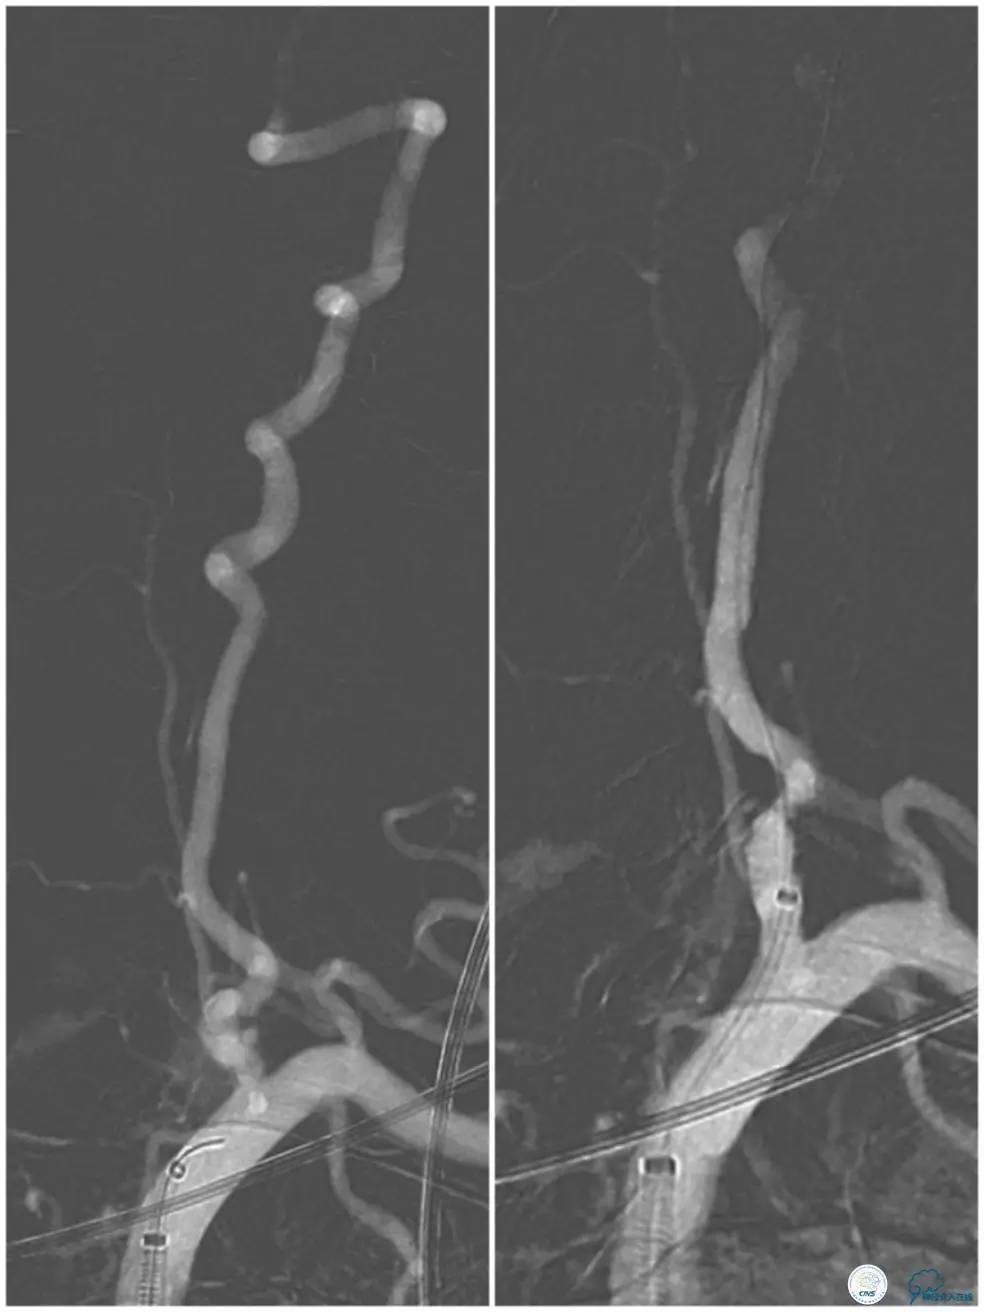

全麻下右侧股动脉穿刺置入8F动脉鞘,交换技术送入7F Cook长鞘(70cm)+6F Navien(115cm),长鞘置于左锁骨下动脉近端,Navien置于左椎动脉开口处。沿Navien送入Traxcess(0.014″200cm)微导丝+Echelon-10微导管指左椎动脉V3段,此时拟跟进Navien导管进入左椎动脉V2段,但反复尝试均未获成功(图8)。

图8